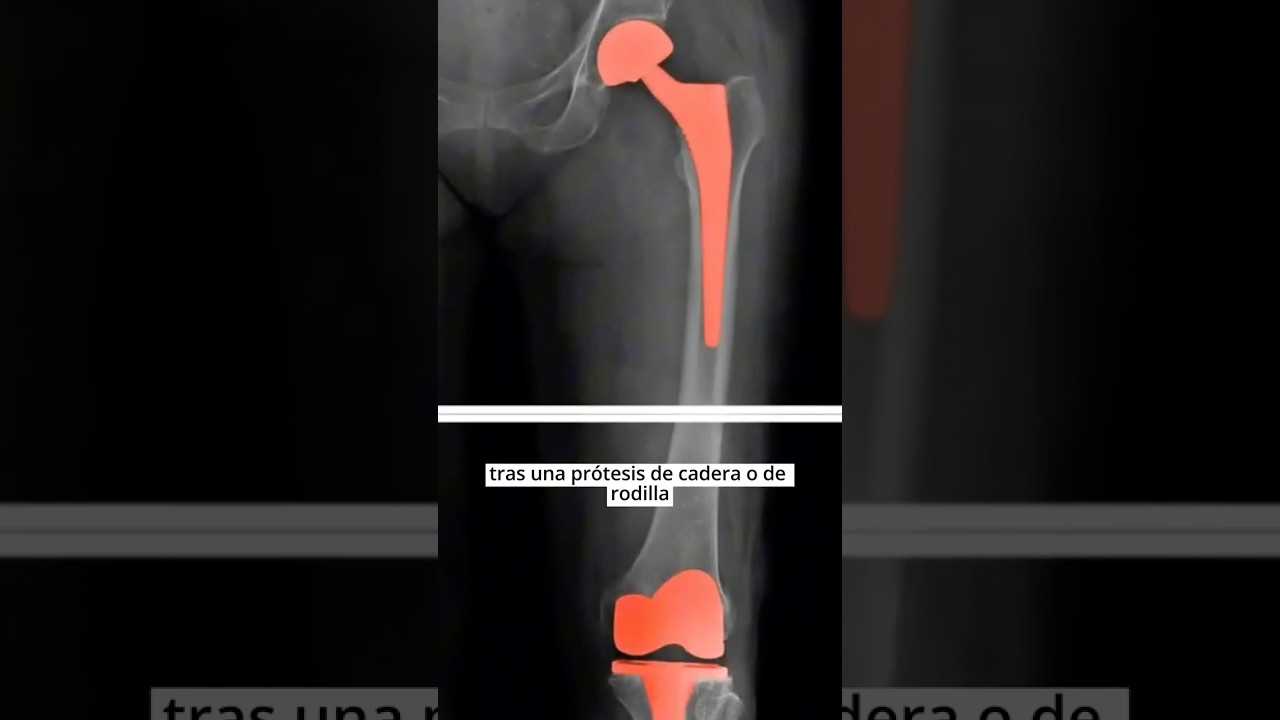

Una prótesis de cadera es un dispositivo artificial que reemplaza la articulación natural dañada por enfermedades como la artrosis, fracturas o procesos degenerativos. Está diseñada para restaurar la movilidad y reducir el dolor, permitiéndote recuperar muchas de las actividades diarias que antes resultaban difíciles.

La cirugía implica la sustitución del acetábulo (parte del hueso de la pelvis) y la cabeza femoral por componentes metálicos, plásticos o cerámicos que simulan la función de la articulación original.